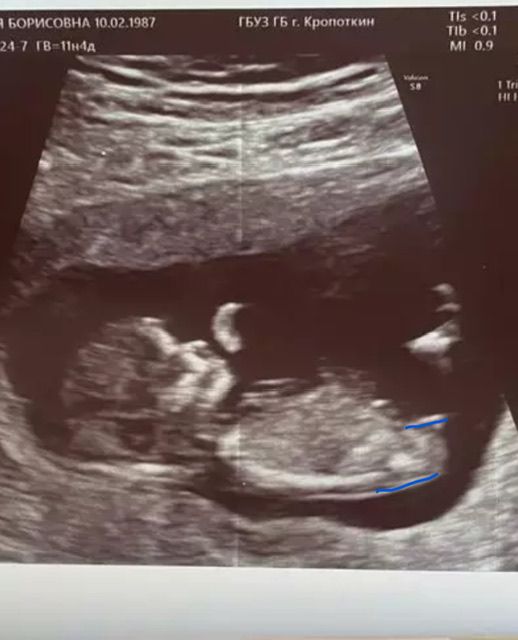

Мальчик или девочка???

Видите, бугорок четко параллелен позвоночнику?)) Девочка точно)) Я с такой же фоткой своей 3й дочки неделю здесь просидела, в надежде найти там мальчика 😂

По полосочке точно девочка

Я б сказала, что мальчик по снимку. Но, раз вы сдали анализ, то мало ли что мы тут по снимку видим. А второе, я снимала в 12 недель видео. Моя врач разрешила. И хотя она мне в подробностях рассказала почему у меня девочка, а не мальчик,все равно, на некоторых кадрах был прям мальчиковый бугорок🤣. Еле дожила до 16 недель и кофейного зернышка. Верьте крови

Софа, даже если забыть про анализ, то у мальчиков сильнее все же вверх торчит, я бы подумала что тут девочка

Я девочку вижу ,персик 😀

Девочка, у моей также торчало))